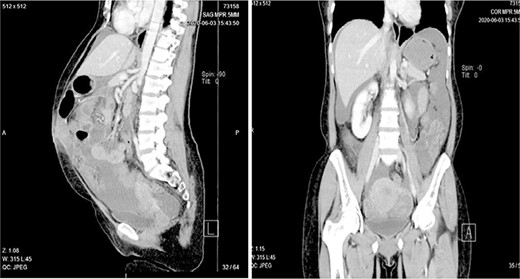

Abdominal pelvic ultrasound revealed ascitic fluid and enlarged uterus. Chest X-ray (Fig. 1) was normal. Computed tomography (Fig. 2) revealed cystic mass arising from left ovary measuring 15.6 × 7.1 × 6.1 cm with multiple soft masses in mesentery, omentum and umbilicus. Diagnosis of left ovarian tumor with peritoneal metastasis was suggested.

Computed tomography showing a complex cystic mass arising from left ovary with heavy mesentery metastasis.